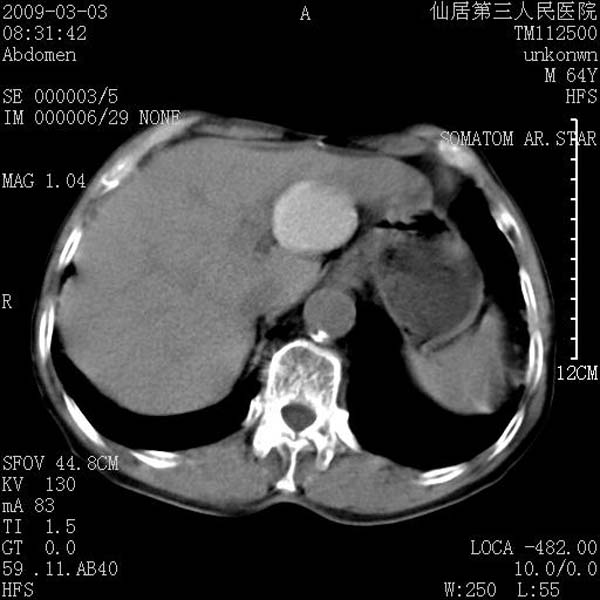

标题: CT18469:男性,64y,体检B超示肝脏低回声肿块,有胃溃疡手术 [打印本页]

患者,男性,64y,体检b超示肝脏低回声肿块,有胃溃疡手术史。

考虑----胃肠道间质瘤可能性大

考虑胃间质瘤可能性大。

胃肠道间质瘤!

考虑肝静脉韧带裂区良性占位性病变(囊肿?)。

考虑肝囊肿并出血可能性大.

考虑高密度囊肿可能性大